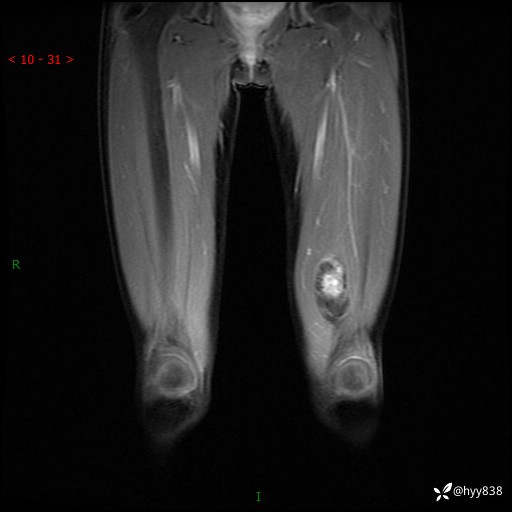

左大腿MRI平扫+增强